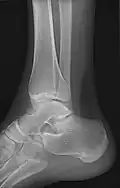

• Ankle - AP/Mortice and Lateral

• Foot / Toes - Dorsoplantar, Oblique and Lateral.[19]